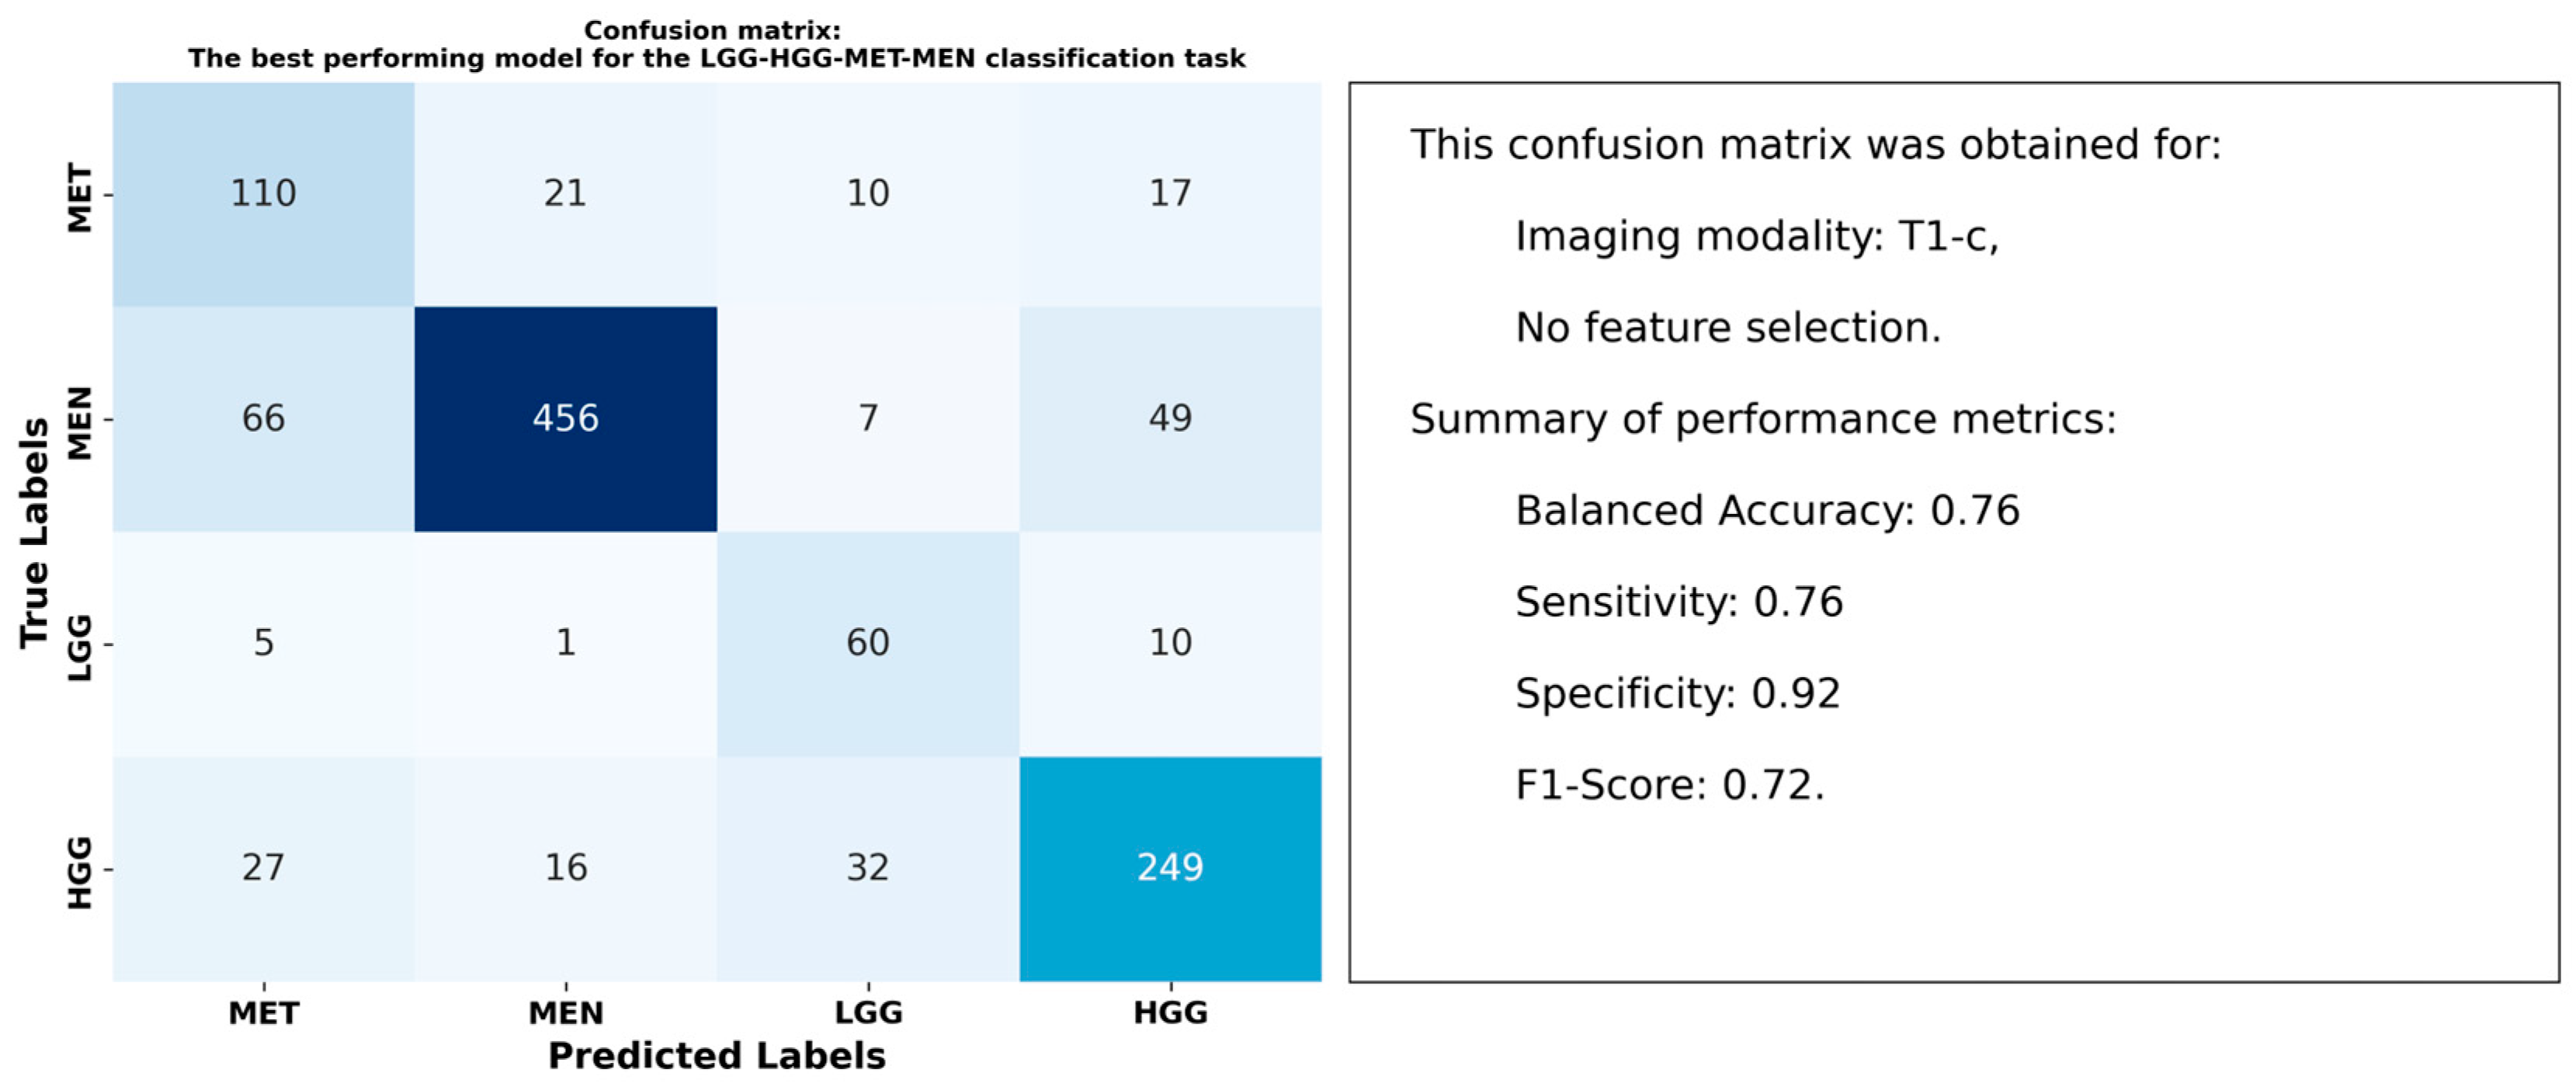

3.3. Results for the LGG-HGG-MET-MEN Classification Task

4.2. Optimal Models and Superior Performance of T1-c Features

4.4. Interpretation of Radiomic Features Using SHAP Analysis